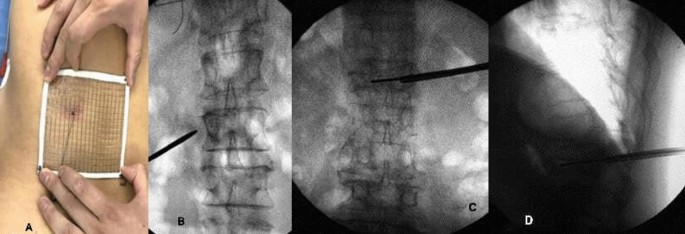

The prone patient was given local anesthesia (lidocaine with a dose of 50–100 mg per patient), sterilized, and punctured at the preoperatively planned skin puncture spot (point A) (Fig. 2A). We found the spinal bone puncture point by "C" arm X-raying the "outside edge of the pedicle" and the transverse process's tangent line (point B, Fig. 2B). The core is removed, and the guidewire is implanted when the puncture needle tip reaches the inner pedicle. The guidewire tip touches the vertebral body's anterior edge and the contralateral pedicle's inner edge at the target site (point C, Fig. 2B). After checking the puncture path and crucial puncture spots, we inserted the working channel and applied bone cement.

(A) X-ray showing that the bone cement was fully diffused into the vertebral body in the mesh optimization group, (B) X-ray showing the healing of injured vertebral body.

Bone cement injection volume

In the mesh optimization group, the bone cement was fully diffused into the vertebral body (Fig. 3), of which the injection volume was (5.3 ± 2.1) ml; In the traditional PVP group, the bone cement was diffused into the puncture site, but the opposite side was not fully diffused (Fig. 3), of which the injection volume was (4.4 ± 1.5) ml. There was a significant difference in the amount of bone cement injected between the two groups (t = 1.738, P = 0.048). The amount of bone cement injected in the mesh optimization group was higher by 20.5% than in the traditional PVP group.

(A) X-ray showing that the bone cement was diffused into the puncture site in the traditional PVP group, (B) X-ray showing the contralateral side was not fully diffused.